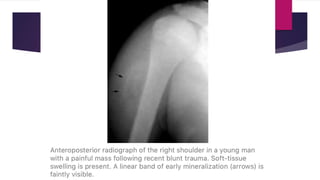

 Radiograph – normal or soft tissue density seen.

 Radiograph – “Dotted veil” calcification (confusing with

rhabdomyosarcoma or synovial sarcoma). There may be continuous or

discontinuous peripheral calcification.

Stages of disease Early disease (inflammatory phase)  Pain and swelling (mimics infection or soft tissue aggressive tumor).  Radiograph – normal or soft tissue density seen.  USG – hypoechoic mass with a central reflective core is seen that may have a lamellar hyper reflectivity at the periphery of mass.  CT scan – enlarged muscle growth with normal attenuation.  MRI – isointense to hyperintense on T1 weighted images and intermediate to high signal on T2 weighted images.